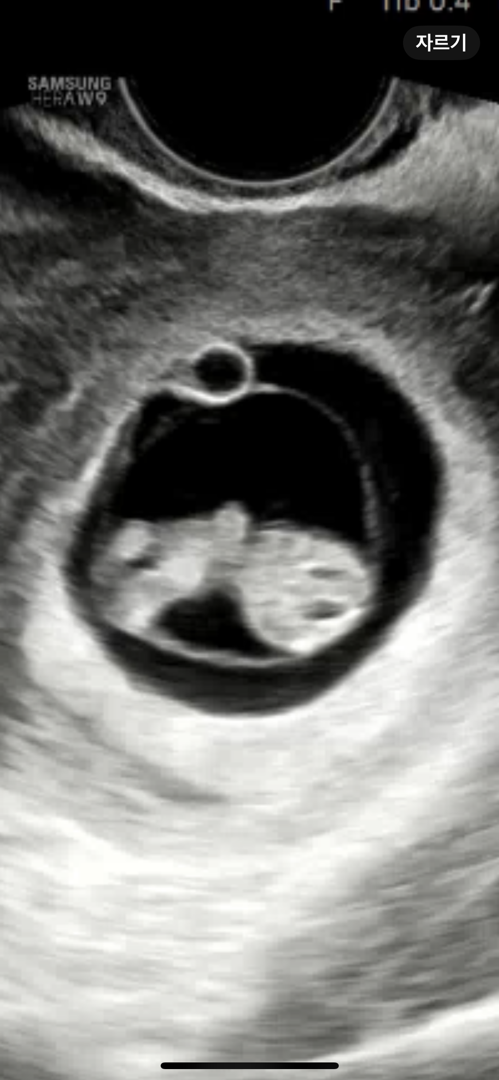

8주3일차 쑥쑥이🎀

난임병원 졸업후 일반산부인과 첫 초음파 보고왔어요! 주수보다 크다고 9주정도 크기라고 하셨어요! (쌤께서 오동통~하다고 해주셨어요ㅎㅎ) 입덧먹덧양치덧 힘든와중에 통통하게 잘크고있어서 마음이 놓여요☺️ 봐도봐도 너무 귀여워요 ㅠㅠㅠ